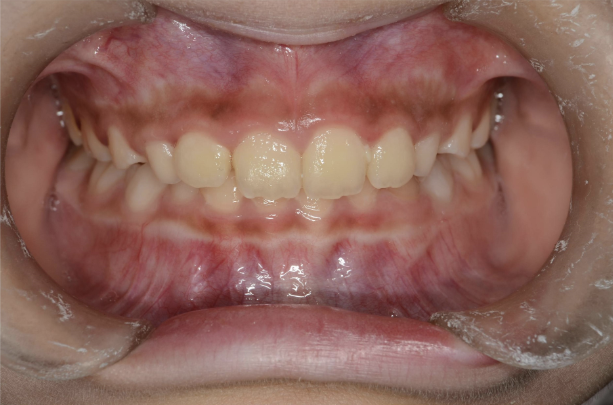

お子さんが「矯正治療」をはじめる時に直面する問題は 「装置が目立つ」、 そして「歯を抜く」ことがあげられます。

10歳を超えてからの治療開始ではそのようにならざるを得ないことが多いのです。

しかしながら、5〜7歳頃に治療をスタートすれば 目立ちにくい装置で、歯を抜かずに治療できることがあります。

10歳を過ぎてからの矯正治療の場合、大人の歯を抜いて治療することが多くなります。 一方、下の前歯が生えてくる5〜7歳頃から治療を始めると、大人の歯を抜かずに治療することが可能です。 抜かずに治療するには早期に治療を開始することが大切です。